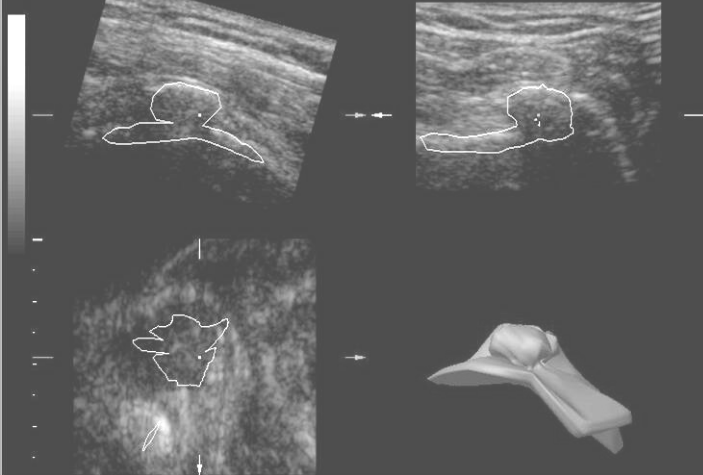

Obr.1

Baker’s cyst – by means of cutting of the cube of information is possible to find the place of interest: in this case the communication between joint and cyst cavity

Obr. 1

Synoviální pseudocysta

Prořezáním krychle informací je možno exaktně zachytit oblast zájmu – zde místo komunikace mezi kloubem a dutinou pseudocysty